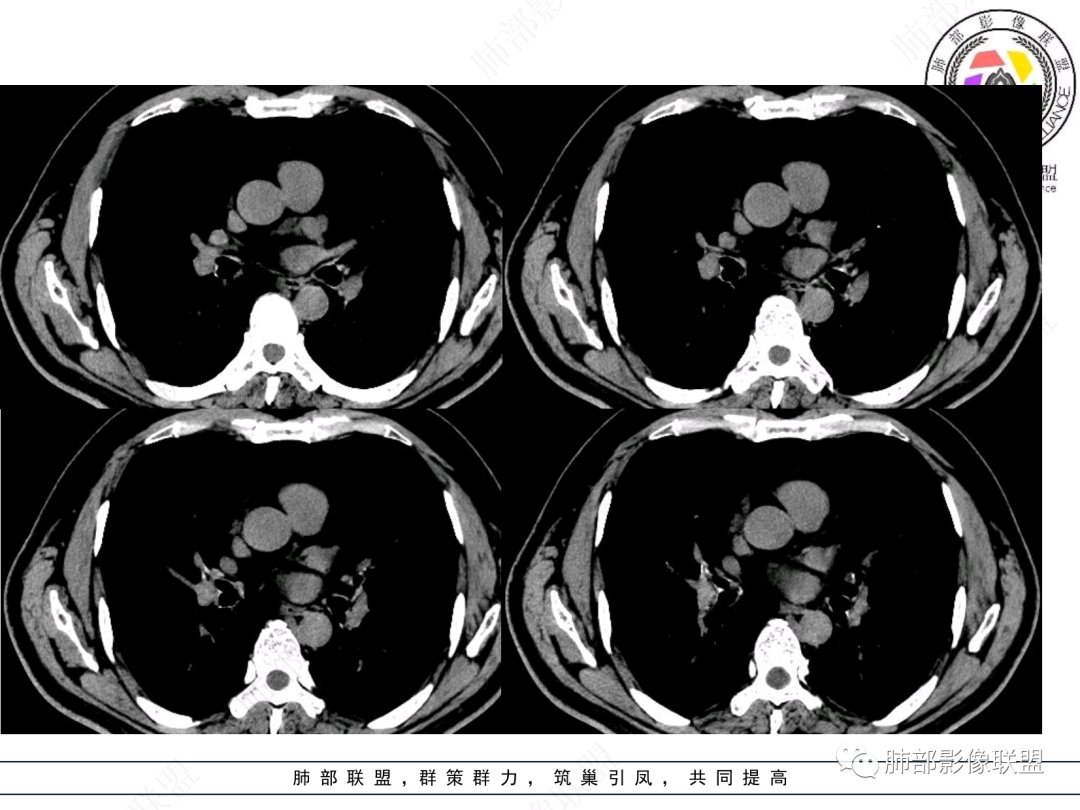

右肺上叶支气管截断,内见软组织密度结节,支气管管壁破坏,病变侵及管外,增强强化明显。右肺上叶沿气管血管束多发斑片影,考虑恶性性病变并阻塞性炎症,鳞癌,神经内分泌肿瘤。

右主支气管及肺门不规则软组织结节,点状钙化,不均匀强化,气管壁破坏,上叶支气管阻塞,分支粘液栓,血管束增粗,沿支气管分布多发结节,考虑鳞癌合并阻塞性炎症,鉴别结核。

男性,52岁,右侧主支气管腔内外占位伴点状钙化,病灶大部分位于腔外,右肺上叶散在结节影,气管腔内病灶,动脉期中度强化,静脉期强化减低,首先考虑气管腔内类癌可能,鉴别鳞癌,肺内病变倾向感染性病变;再有气管结核伴肺内播散。

屈运良:

右上叶支气管闭塞,腔内可见软组织肿块,右肺门见肿大淋巴结,远端有阻塞性肺炎,右肺门肿块不均匀强化,其内血管侵蚀边缘模糊,定性恶性,考虑鳞癌或腺样囊腺癌

如果在这种情况下临床想通过CT了解啥?主要是:a、与附近结构的关系:血管、淋巴结;b、远端情况;c、其他区域转移情况;